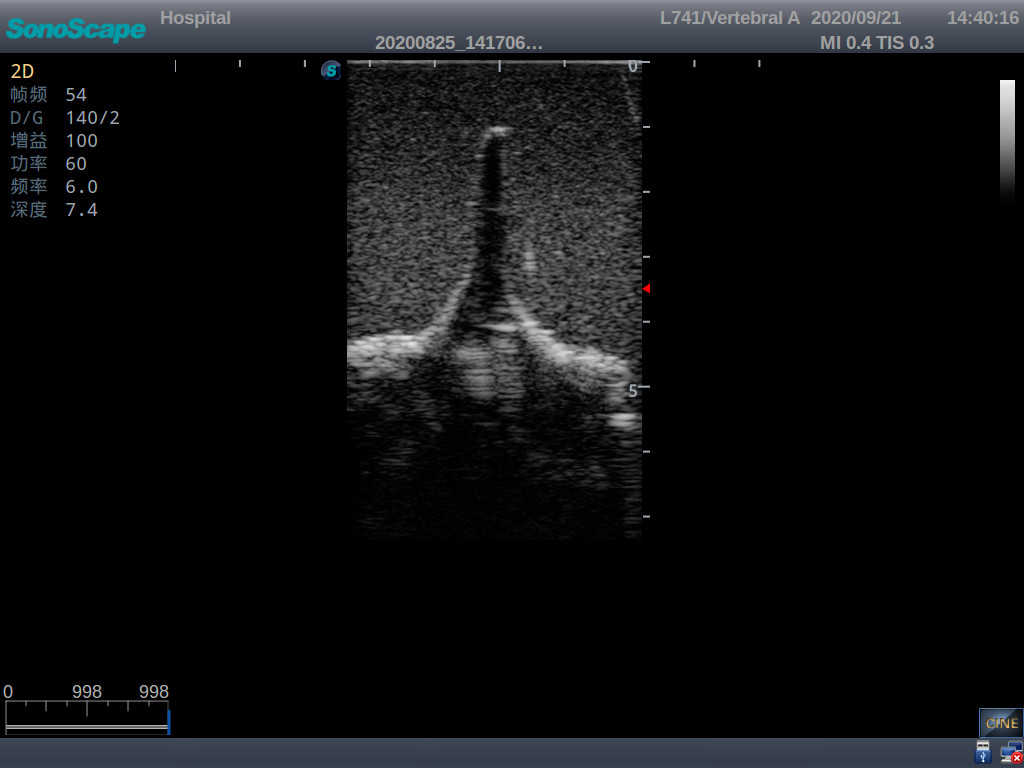

Adult Lumbar Puncture Ultrasound Training Model

This model is an ideal choice for ultrasound-guided adult lumbar puncture training with true-to-life skin feel and touch, accurate anatomical structures as well as real clinical ultrasound images. Realistic resistance to needle tips and correct landmarks provide excellent hands-on experience.

Accurate anatomical structure of L1-L5 and the vertebral canal

2)  Real clinical ultrasound images

1)   Ultrasound-guided lumbar puncture practice